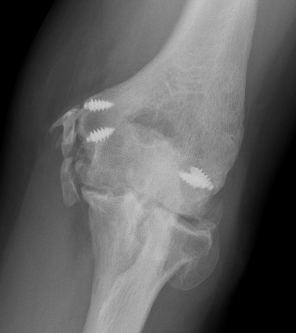

Elbow dislocation with coronoid process fracture

Coronoid process

Coronoid is the most important portion of ulno-humeral articulation

- provides anterior buttress

- attachment of capsule and brachialis

- anterior band of the MCL attaches to it

Fixation

Lasso suture - suture fragment, use ACL guide to direct drill holes through olecranon to base of coracoid

Screws - PA screws into fragment

Buttress plate

Coronoid buttress plates

1. Restore coronoid stability - ORIF type II / III, suture repair type I